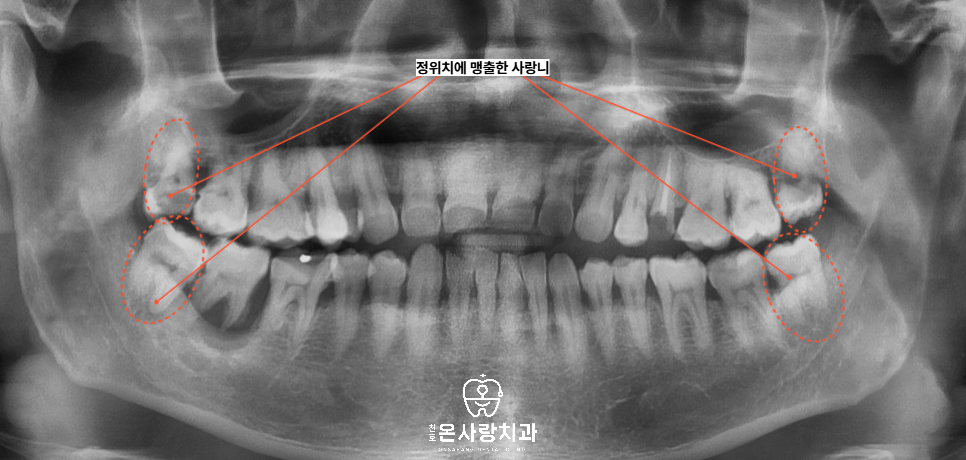

이번 환자분 역시 천호동사랑니가

방향은 바르게 나있었지만

구강 구조상 뒤쪽 청소가 어려워

오랜 시간 충치와 염증이

누적된 상태였습니다.

그 결과 왼쪽 위 어금니를 제외한

상악과 하악의 어금니 대부분이

사랑니의 영향 아래 있었고

뒤쪽에서부터 앞쪽 치아로

문제가 확산되는 흐름을 보였습니다.

사랑니를 보면 다른 치아와비교했을 때

맹출방향이나 위치가 정위치에 있습니다.